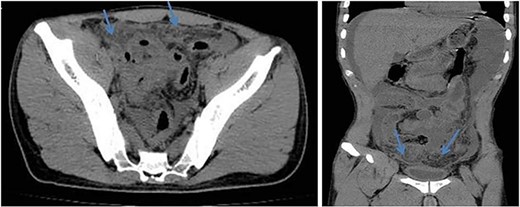

Axial (left) and coronal (right) views of abdomen CT scan without contrast show dirty fat planes closely related to the urinary bladder walls (mass formation).